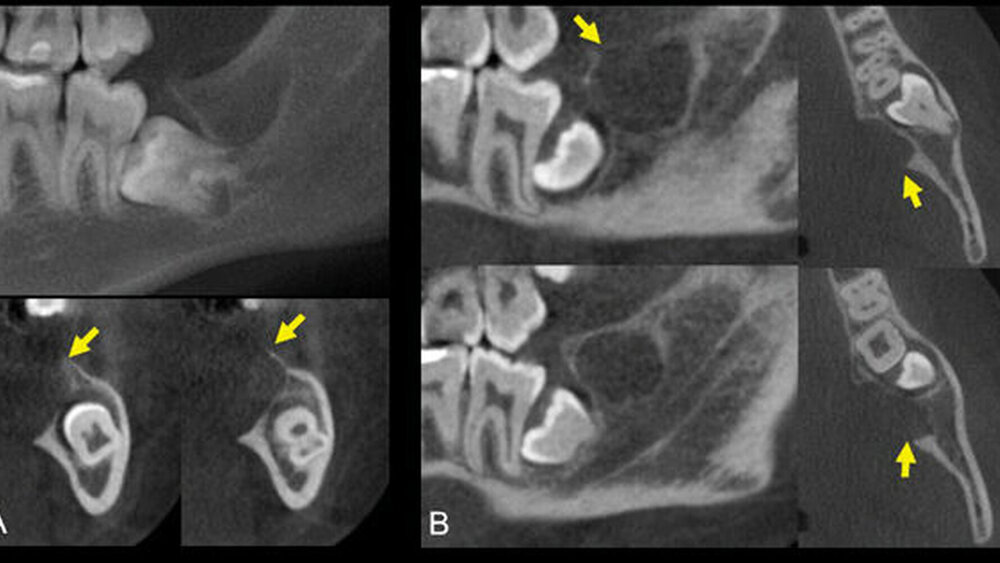

Forschende aus Brasilien berichten über eine junge Patientin, die mit einer Schwellung im linken Unterkiefer Regio 38 vorstellig wurde. Die Siebzehnjährige hatte keine Schmerzen und konnte nicht sagen, seit wann die Schwellung bestand. Im der Bildgebung imponierte eine „osteolytische Läsion mit definierten Grenzen in Bezug auf die Nähe zum perikoronalen Follikel des Zahnes 38“, was zur Verdachtsdiagnose einer odontogenen Läsion führte [Teixeira et al., 2023]. Im Anschluss wurde eine Inzisionsbiopsie durchgeführt, deren pathologische Untersuchung ein nicht abgekapseltes Neoplasma drüsigen Ursprungs bestehend aus Schleim-, Intermediär- und Plattenepithelzellen mit überwiegend zystischem Wachstum ergab, was laut der Autoren auf ein intraossäres mukoepidermoides Karzinom schließen lässt. Der Tumor wurde in der Mund-, Kiefer- und Gesichtschirurgie entfernt. Auch vier Jahre nach dem Eingriff gibt es keinen Hinweis auf ein Rezidiv.

Teixeira et al. benennen sechs diagnostische Kriterien für die CMEC-Diagnose: das Vorhandensein einer intakten Kortikalisplatte, eine radiologisch eindeutige osteolytische Läsion, eine positive Muzinfärbung, das Fehlen einer Primärläsion in der Speicheldrüse, ein Ausschluss eines odontogenen Tumors oder einer Metastase sowie die histologische Bestätigung [2023]. Im vorliegenden Fall wurden, bis auf die intakte Kortikalis, alle Kriterien erfüllt. Weil die meisten Autoren die Kortikalis allerdings lediglich in konventionellen Röntgenbildern und nicht in einer 3-D-Bildgebung beurteilt haben, halten Teixeira et al. dieses Kriterium für fraglich. Sie verweisen auf eine Arbeit, die empfiehlt, beim gleichzeitigen Vorliegen interner sklerotischer Knochenmassen und Perforation der externen Kortikalis mit Ausdehnung in das umgebende Weichgewebe ein CMEC in Betracht zu ziehen [Chan et al., 2013, Teixeira et al., 2023].